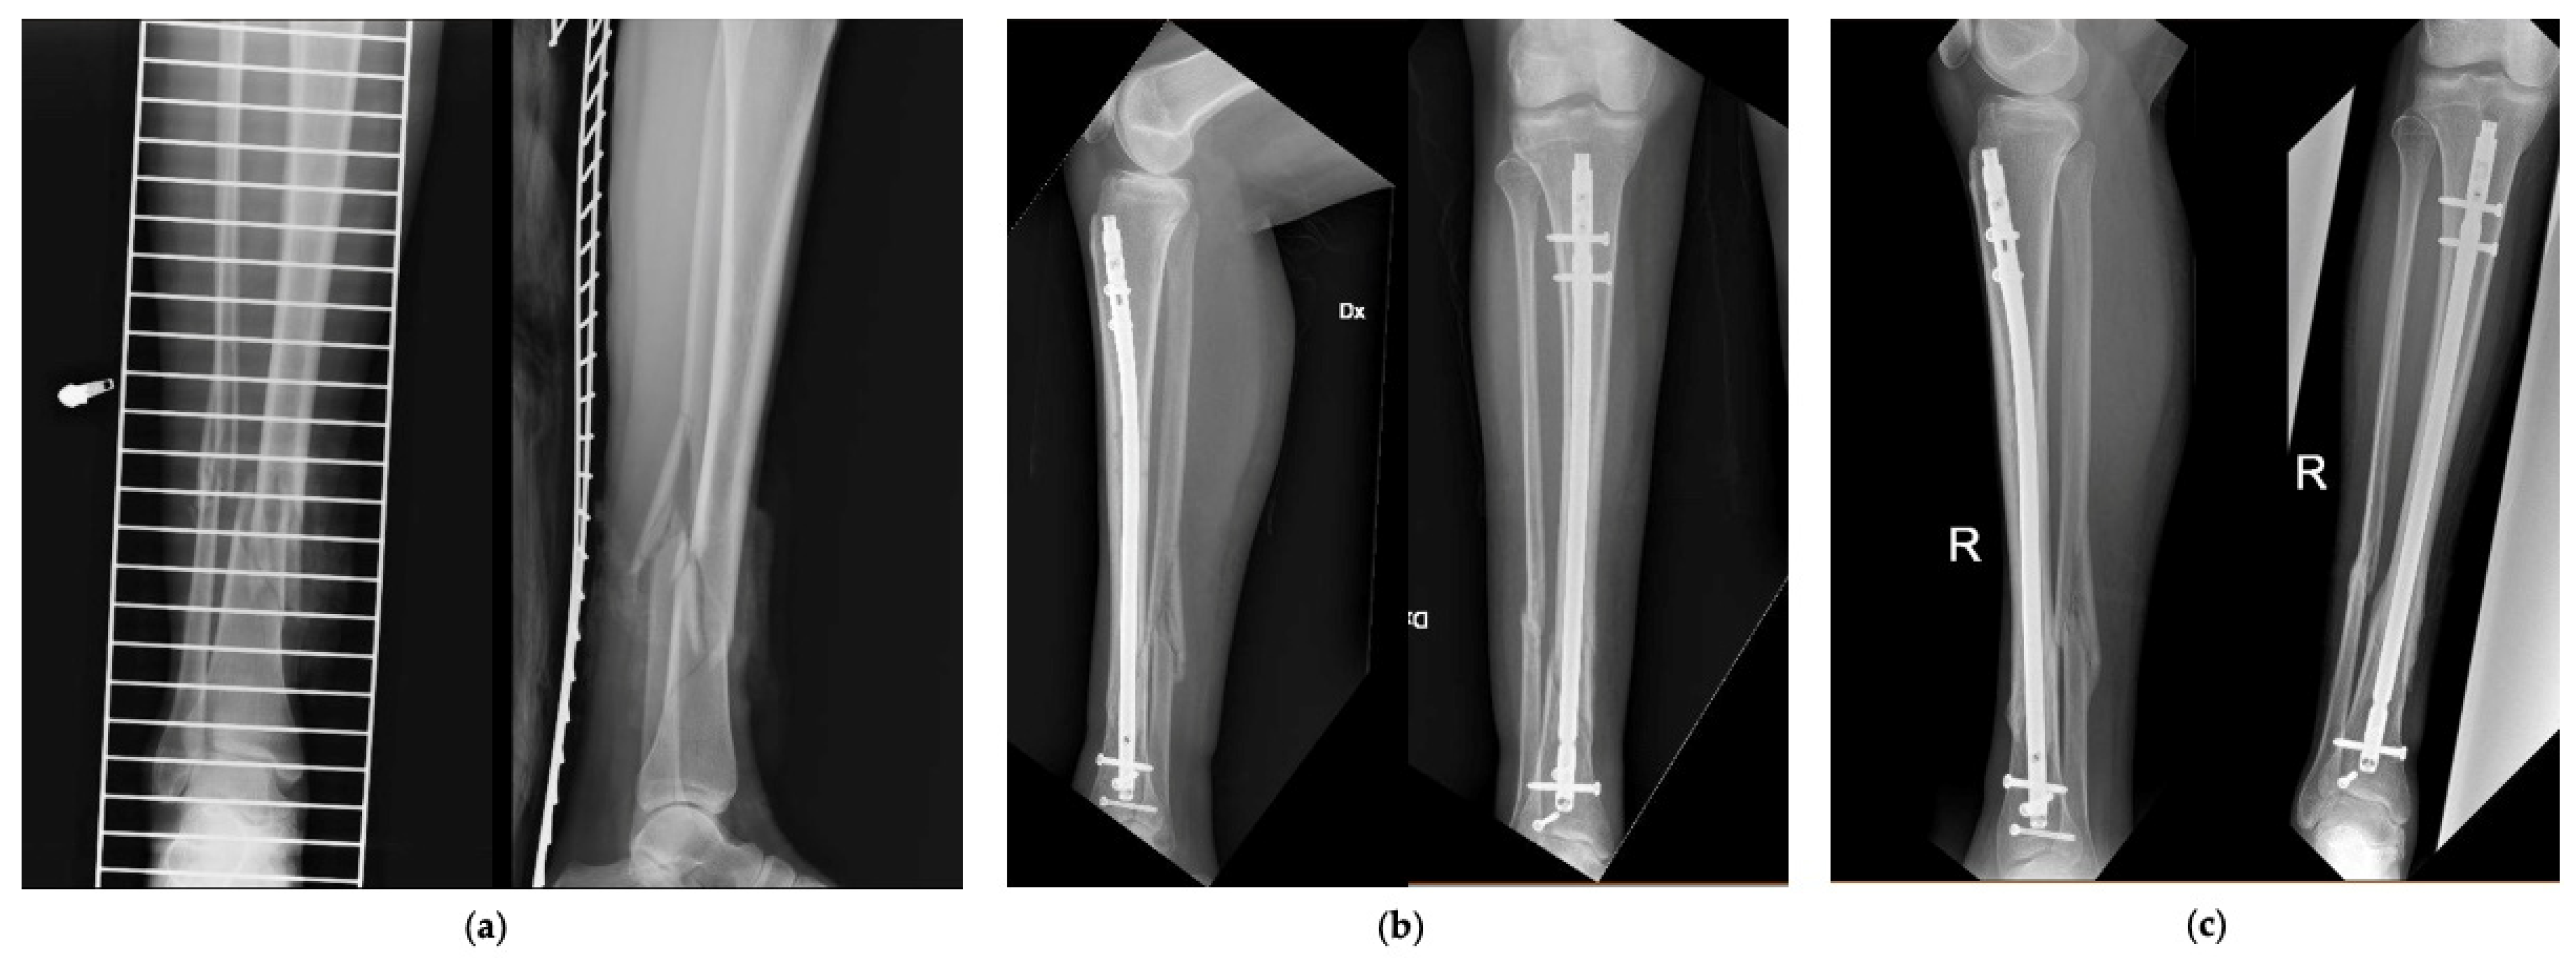

Figure 2 and Figure 3 show 2 clinical cases of the series, with pre-operative and follow-up radiographic images.

Figure 2.

Patient number 27 of the series. (a) Pre-operative AP and LL X-rays, (b) AP and LL X-rays at 6 months, (c) AP and LL X-rays at 12 months.